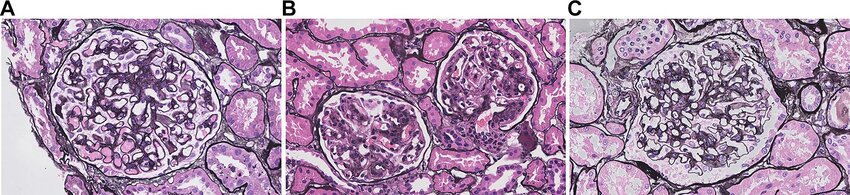

HBV 항원이 사구체에 침착되면서 발생하는데, 특히 소아 남아에서 흔한 막성 신병증(MGN) 형태가 대표적입니다.

병리 소견에서 HBsAg, HBcAg, HBeAg, HBV DNA가 사구체 병변 부위에서 발견됩니다.

신장에 미치는 영향의 형태가 대표적 형태 막성 신병증(MGN, Membranous glomerulonephritis) 형태입니다.

기타 형태로

국소분절 사구체경화증(FSGS)

막증식 사구체신염(MPGN)

메산지움 증식 사구체신염